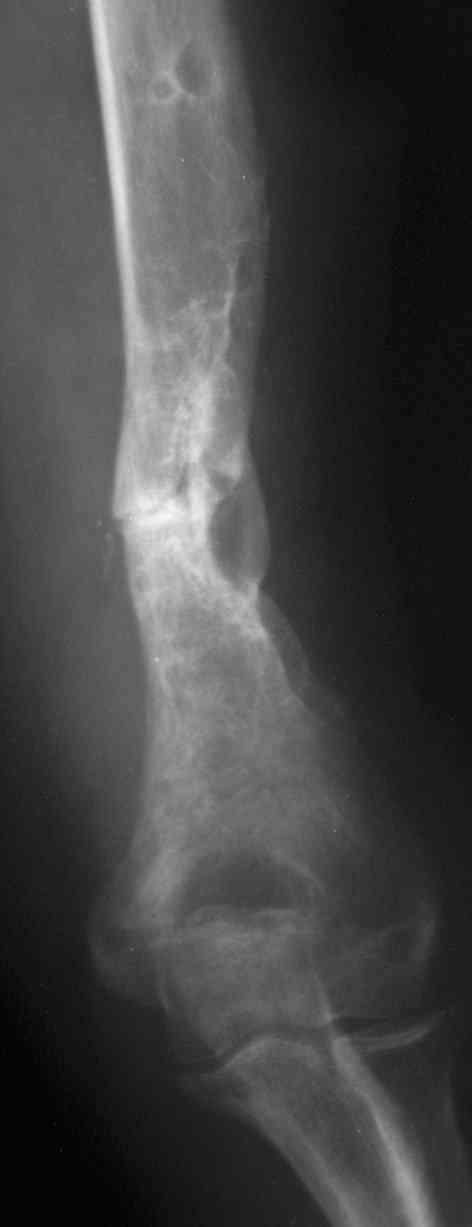

[Ortho] ложный сустав после остеосинтеза плеча

В подобном случае мы бы применили  чрескостный остеосинтез. Пример - в

приложении.